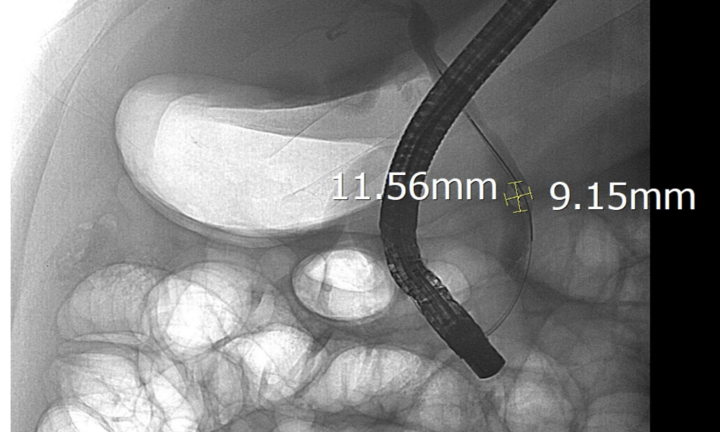

Đau bụng, vàng da kéo dài, men gan tăng cao, bệnh nhân 44 tuổi được xác định tắc mật do sỏi ống mật chủ và can thiệp kịp thời bằng ERCP.